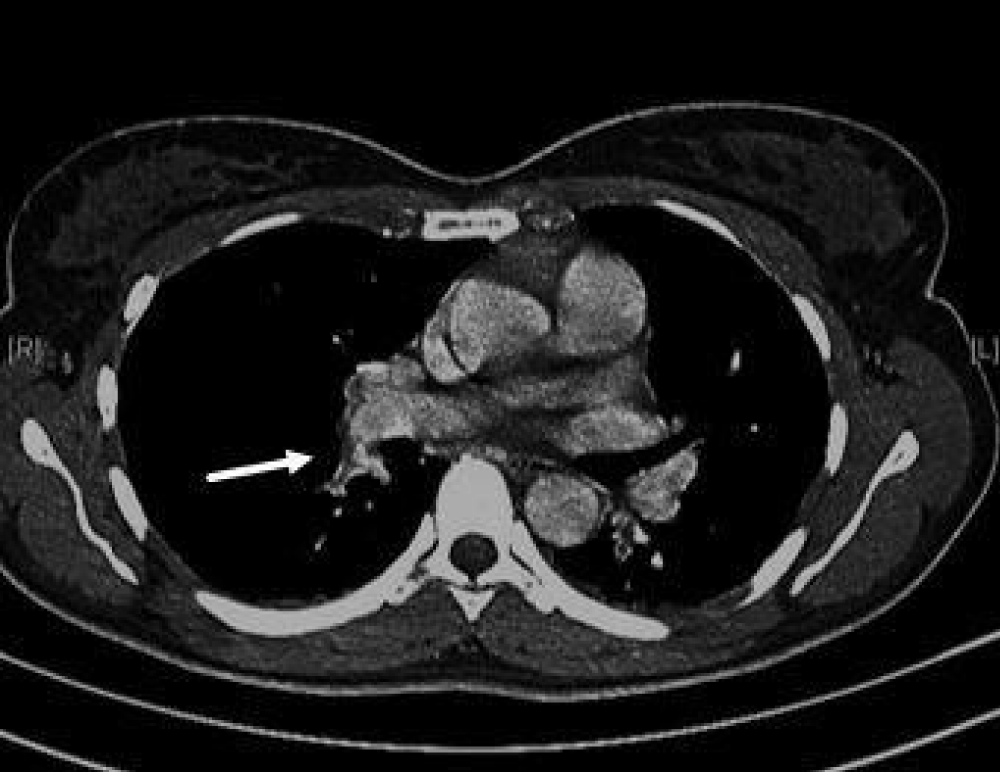

There were no signs of Deep Venous Thrombosis (DVT) such as unilateral leg swelling or pain. However, based on her medical history (oral contraceptive, recent EPS through femoral vein access), laboratory tests (elevated D-dimer), and symptoms (chest pain and dyspnea), a thoracic Computed Tomography (CT) with intravenous iodine contrast medium wasalso performed, revealing an acute right sub-segmental PE (Figure 1).

Figure 1: Pulmonary CT with contrast which shows filling defects in the right sub segmental pulmonary artery compatible with local thrombosis.